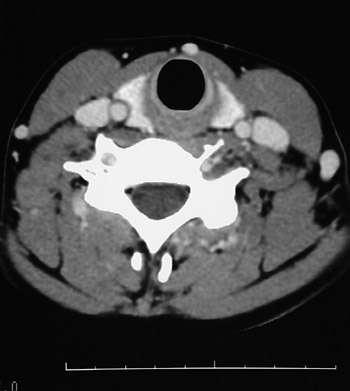

This is a normal axial head and neck CT scan demonstrating the thyroid gland and trachea and sternocleidomastoid muscle and external jugular vein and internal jugular vein and common carotid artery.